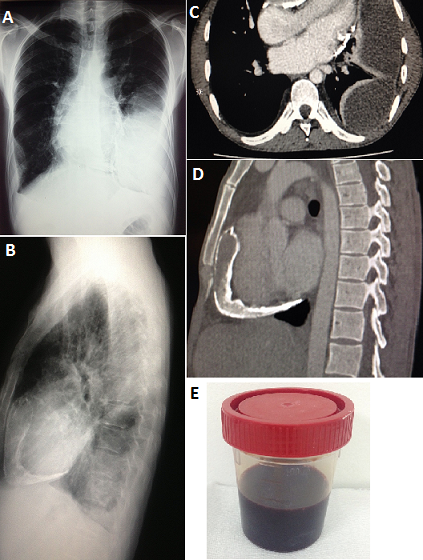

A 38-year-old man was admitted to the hospital for a 2-month gradually progressive history of breath shortness, persistent fever and leg swelling. Two years earlier, he had had a prolonged period of recurrent diarrhea which was spontaneously resolved. On examination temperature was 38.6°C with decreased breath sounds on the left side and leg pitting edema. Laboratory tests showed elevated inflammatory markers without leukocytosis. Chest X-ray revealed pleural effusion with extensive calcifications on the anterior and inferior surfaces of the heart. Thoracic computed tomography confirmed pleural effusion with pericardial thickening and calcification. Echocardiography was suggestive of constrictive pericarditis, thoracenthesis revealed milk chocolate colored pleural fluid containing trophozoites of Entamoeba Histolytica with no mycobacterium or other organisms. The left pleural effusion was drained, patient was administrated Metronidazole IV 500 mg every 8 hours and has done well. Cardiac catheterization confirmed pericardial constriction, and patient received pericardectomy. Analysis Pathological of the surgical specimen did not find arguments for tuberculosis. We then selected the diagnostic of amoebic pleuro-pericarditis.